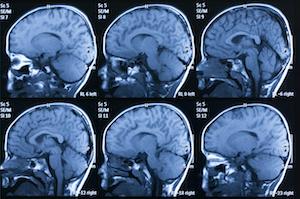

A Traumatic Brain Injury (TBI) usually results from a violent blow or jolt to the head or a penetrating head injury that disrupts the normal function of the brain. A common mild brain injury is often referred to as a concussion. Brain injuries are often permanent and disabling.

According to the ByYourSide.org, a TBI can cause a wide range of functional changes—short or long-term—affecting thinking, language, learning, emotions, behavior and/or sensation. Memory loss, difficulty with judgment and recognition of limitations, anxiety and/or depression, loss of social networking, feelings of isolation, slowness or difficulty with speech, decreased physical coordination, decreased anger management, decreased safety awareness, and difficulty initiating, planning and completing tasks. All of these significant injuries can be the consequences of TBI. In some instances, TBI’s can cause long-term complications leading to attempted suicide or death.

According to the Centers for Disease Control (CDC) each year an estimated 1.5 million Americans sustain a TBI. Approximately 138 people die each day from injuries of a Traumatic Brain Injury. That’s more than 50,000 deaths attributed to TBIs. While 230,000 people are hospitalized and do not suffer a life threatening TBI, 80-90,000 do experience long-term disability. While falls are the leading cause of TBI’s, motor vehicle crashes and traffic related accidents result in the largest percentage of TBI deaths.

In Florida, the number of people living with a TBI is approximately 210,000. Each year 97,000 people sustain a TBI resulting in 3,800 deaths, 18,600 hospitalizations and 74,000 emergency room (ER) visits.

The CDC reports that for people over 65 years of age, falls were the leading cause of TBI death. For children and young adults (5-24 years old) it was motor vehicle accidents, and for children (newborn to 4 years old) assaults (such as Shaken Baby Syndrome) were leading cause of TBI deaths. The leading causes of non-fatal TBIs were falls (newborn to 14 and over 45 years old) and motor vehicle crashes (15-44 years old) and assaults (15-24 year olds).